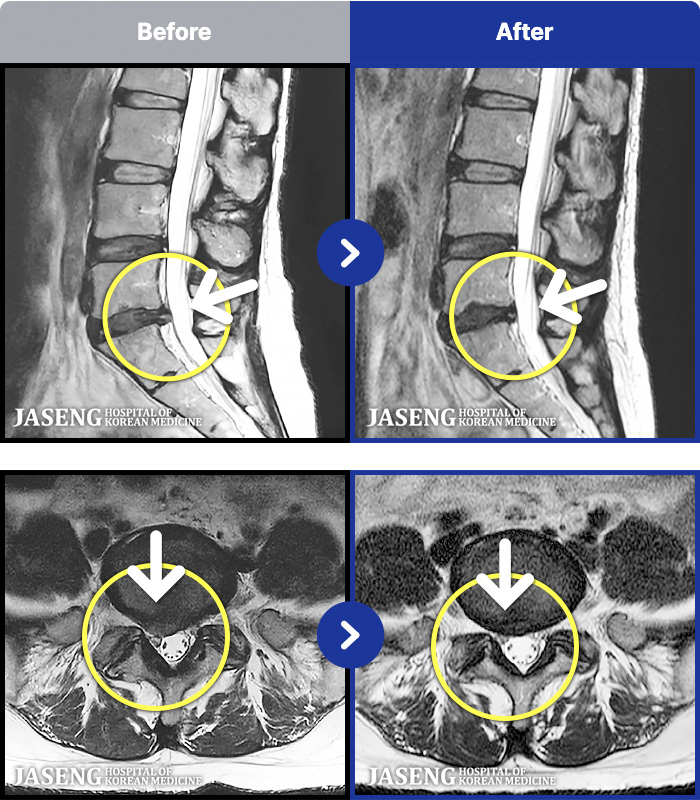

MRI ġ

1,245 MRI ũ ʸ Ȯϼ.